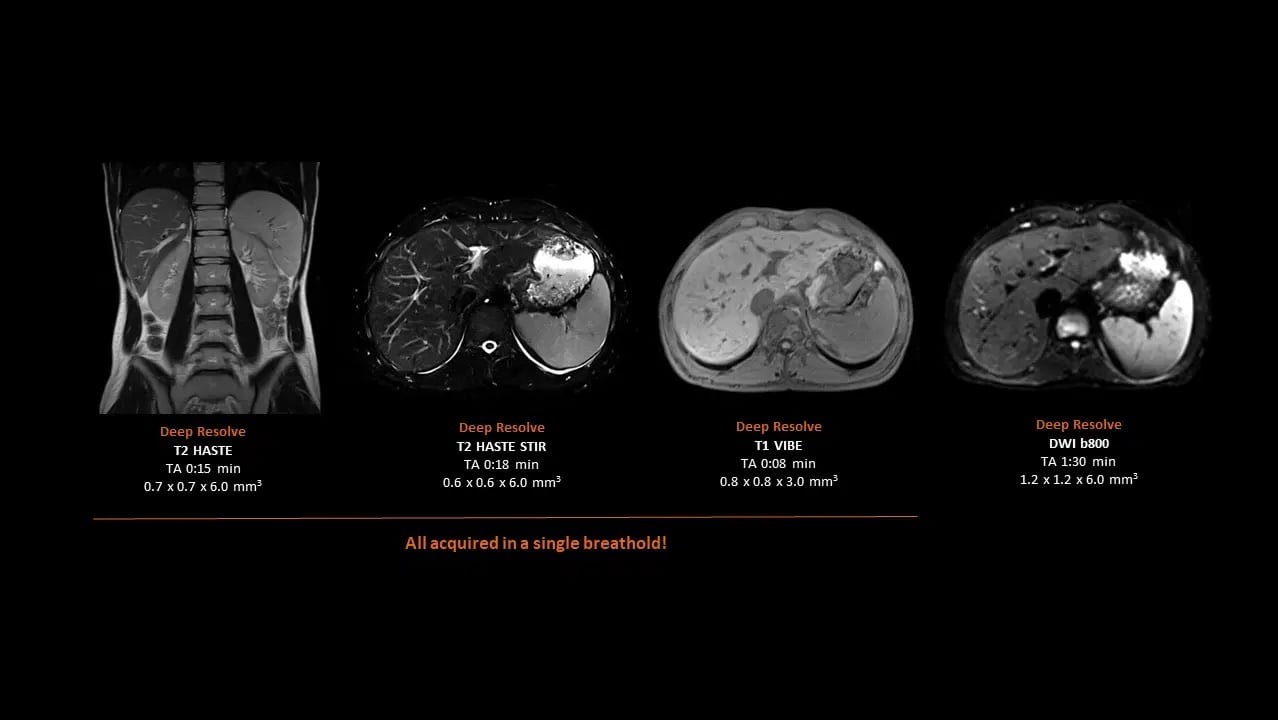

Liver

High-resolution liver imaging with Deep Resolve

Study-ID:1aaaa5325. Acquired on MAGNETOM Flow. Platform with 70cm.

MAGNETOM Flow. Platform Liver

Unrivaled speed with Deep Resolve

Deep Resolve, an AI powered tool used to boost signal and resolution, enables you to exploit advanced acceleration techniques while maintaining extraordinary clarity. Faster scans, faster results, better patient experience!